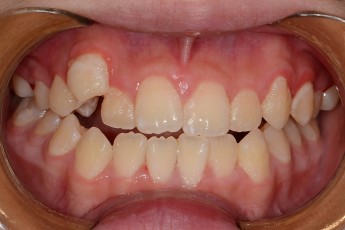

BEFORE & AFTER

- 덧니교정